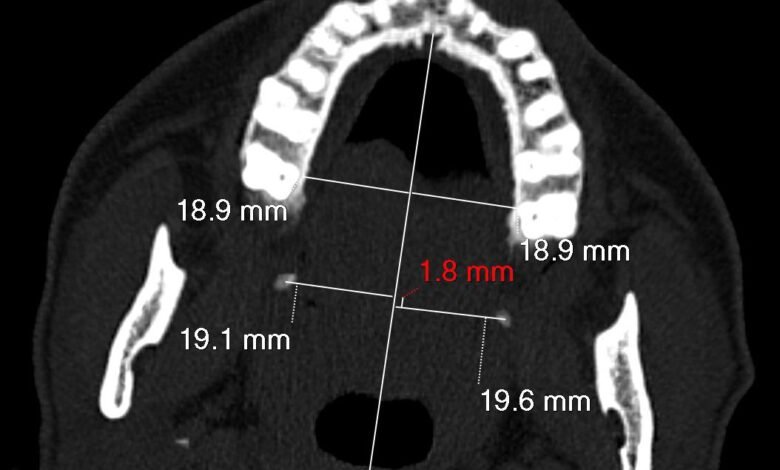

كما كشفت الدراسة عن إمكانية استخدام خط وهمي يتم رسمه على التصوير الطبقي المحوري، أُطلق عليه اسم “Bin Turayki’s Line” نسبة إلى مكتشفه الدكتور هيثم بن عبدالله بن تريكي، ليساهم في تسهيل تشخيص هذه الحالات مستقبلًا.